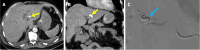

Endoscopic retrograde cholangiopancreatography (ERCP) is a cornerstone procedure for the diagnosis and management of pancreatic and hepatobiliary diseases. Although its diagnostic role has been increasingly supplanted by noninvasive imaging modalities such as magnetic resonance imaging (MRI) and magnetic resonance cholangiopancreatography, the therapeutic applications of ERCP have continued to expand. ERCP is widely used and has a generally favorable safety profile. However, it is important to recognize expected post-procedural imaging findings and serious complications that can arise. The increasing complexity of therapeutic interventions and the growing volume of procedures have led to a higher incidence of complications that often present with overlapping clinical and laboratory features, underscoring the critical role of imaging in differential diagnosis. This review focused on the typical normal ERCP findings and the imaging characteristics of common complications, including pancreatitis, bleeding, ERCP-related infections, perforations, and stent-related complications. Computed tomography (CT) is particularly valuable in timely recognition, management, and surgical decision-making for these complications. Furthermore, MRI offers a radiation-free alternative for managing complications in selected patients. Therefore, radiological modalities, particularly CT and MRI, are critical tools for the rapid diagnosis, management, and surgical decision-making processes for post-ERCP complications.